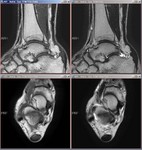

[画像診断]アキレス腱断裂について 2011-03-14